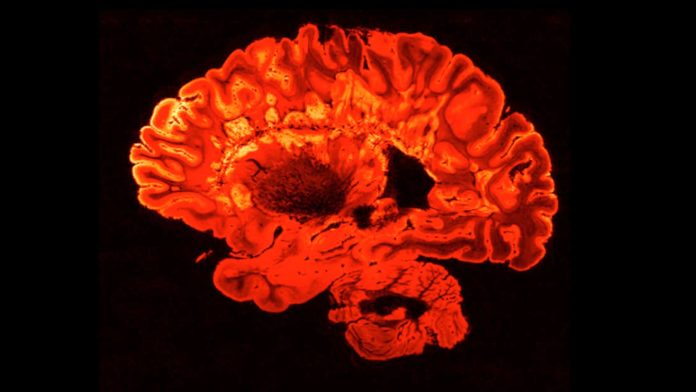

Malia Politzer: After playing the game, the participants lie down in a functional magnetic resonance imaging machine, fMRI, which captures blood flow in the brain.

Nafees Hamid: Depending on where it goes, you can make an inference that that part of the brain is more active for that particular task.

Malia Politzer: While the participants rank these values, the fMRI machine is recording what is happening in a particular part of their brain.

Nafees Hamid: This is a part of the brain; it’s called the left inferior frontal gyrus. It’s oftentimes used for rule processing. It’s normally active when people are processing sacred values. But what we found was that people who were socially excluded, now for their non-sacred values this part of the brain came online.

Malia Politzer: After getting out of the fMRI, the participants retook the survey. They had a choice; they could change their rankings to align with those of their peers, or they could keep them the same. The scientists looked at two specific regions of the brain, one involved in self-reflection and another involved in subjective values.

Malia Politzer: The ARTIS team says that when these active supporters of an extremist group were processing their sacred values, the part of the brain associated with deliberation shut down. And they say it wasn’t working in tandem with the part of the brain associated with subjective values anymore.

Patricia Churchland: Now having said that, it is of course something that the researchers recognize, and that we all recognize, and that is that using functional MRI to explore these kinds of phenomena is the best we can do right now, but it isn’t wonderfully good. You can see some differences at, shall we say, a gross level, and they are significant. But for us to go deeper, we need better kinds of tools to explore the human brain.